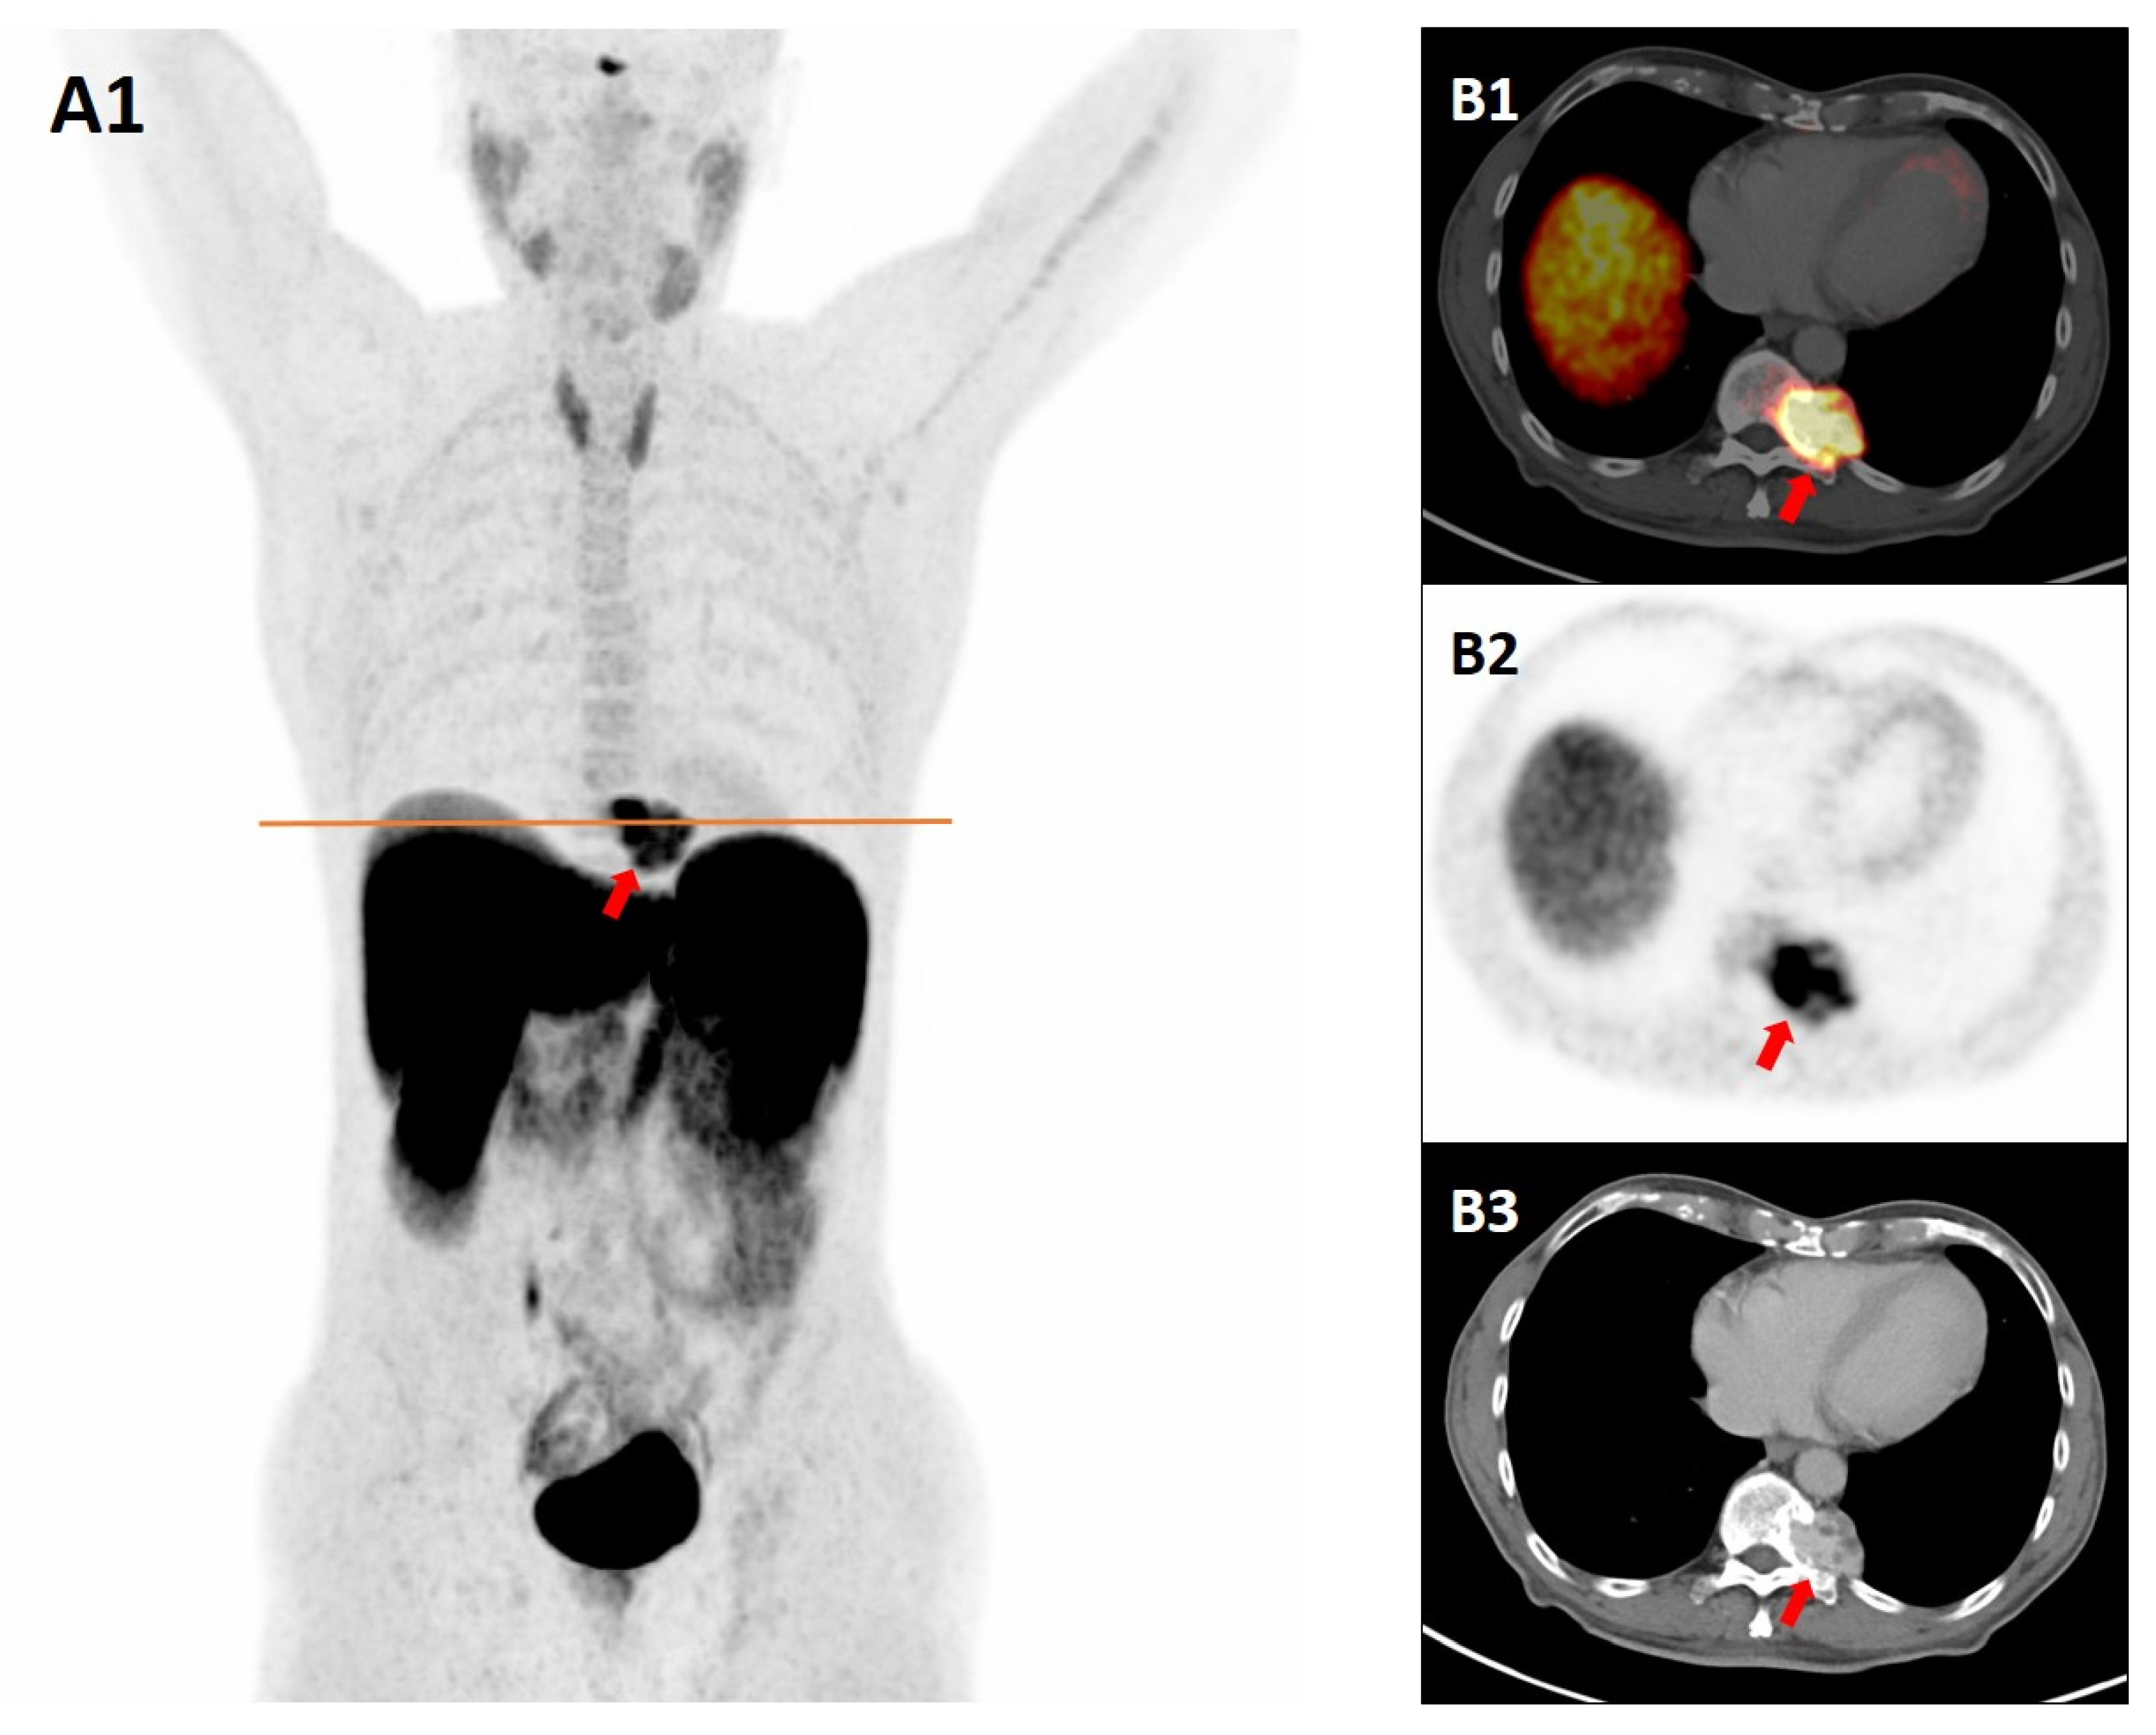

“Not All That Glitters Is Gold”: Paraspinal Cavernous Hemangioma Mimicking Paraganglioma on Somatostatin Receptor PET/CT

Iacovitti, C.M.; Cabrilo, I.; Martinello, C.; Cuzzocrea, M.; Paone, G.; Treglia, G. “Not All That Glitters Is Gold”: Paraspinal Cavernous Hemangioma Mimicking Paraganglioma on Somatostatin Receptor PET/CT. Diagnostics 2025, 15, 2456. https://doi.org/10.3390/diagnostics15192456